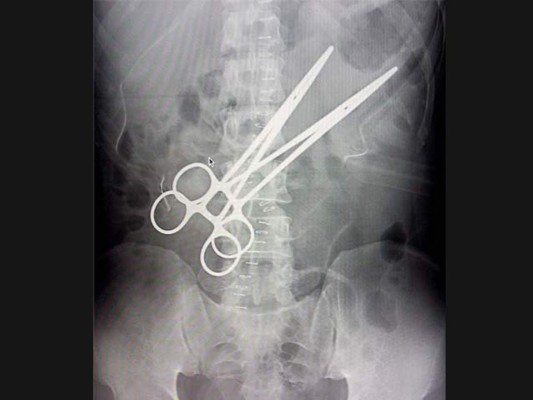

En 2003, una mujer llamada Pat Skinner fue operada del colon en el Hospital Saint George de Sydney, Australia. Dieciocho meses después, insistía en que le dolía el estómago. Las imágenes de rayos X descubrieron una tijeras de 17 centímetros en su cuerpo. 04/12/2019 - 00:006 / 10 -